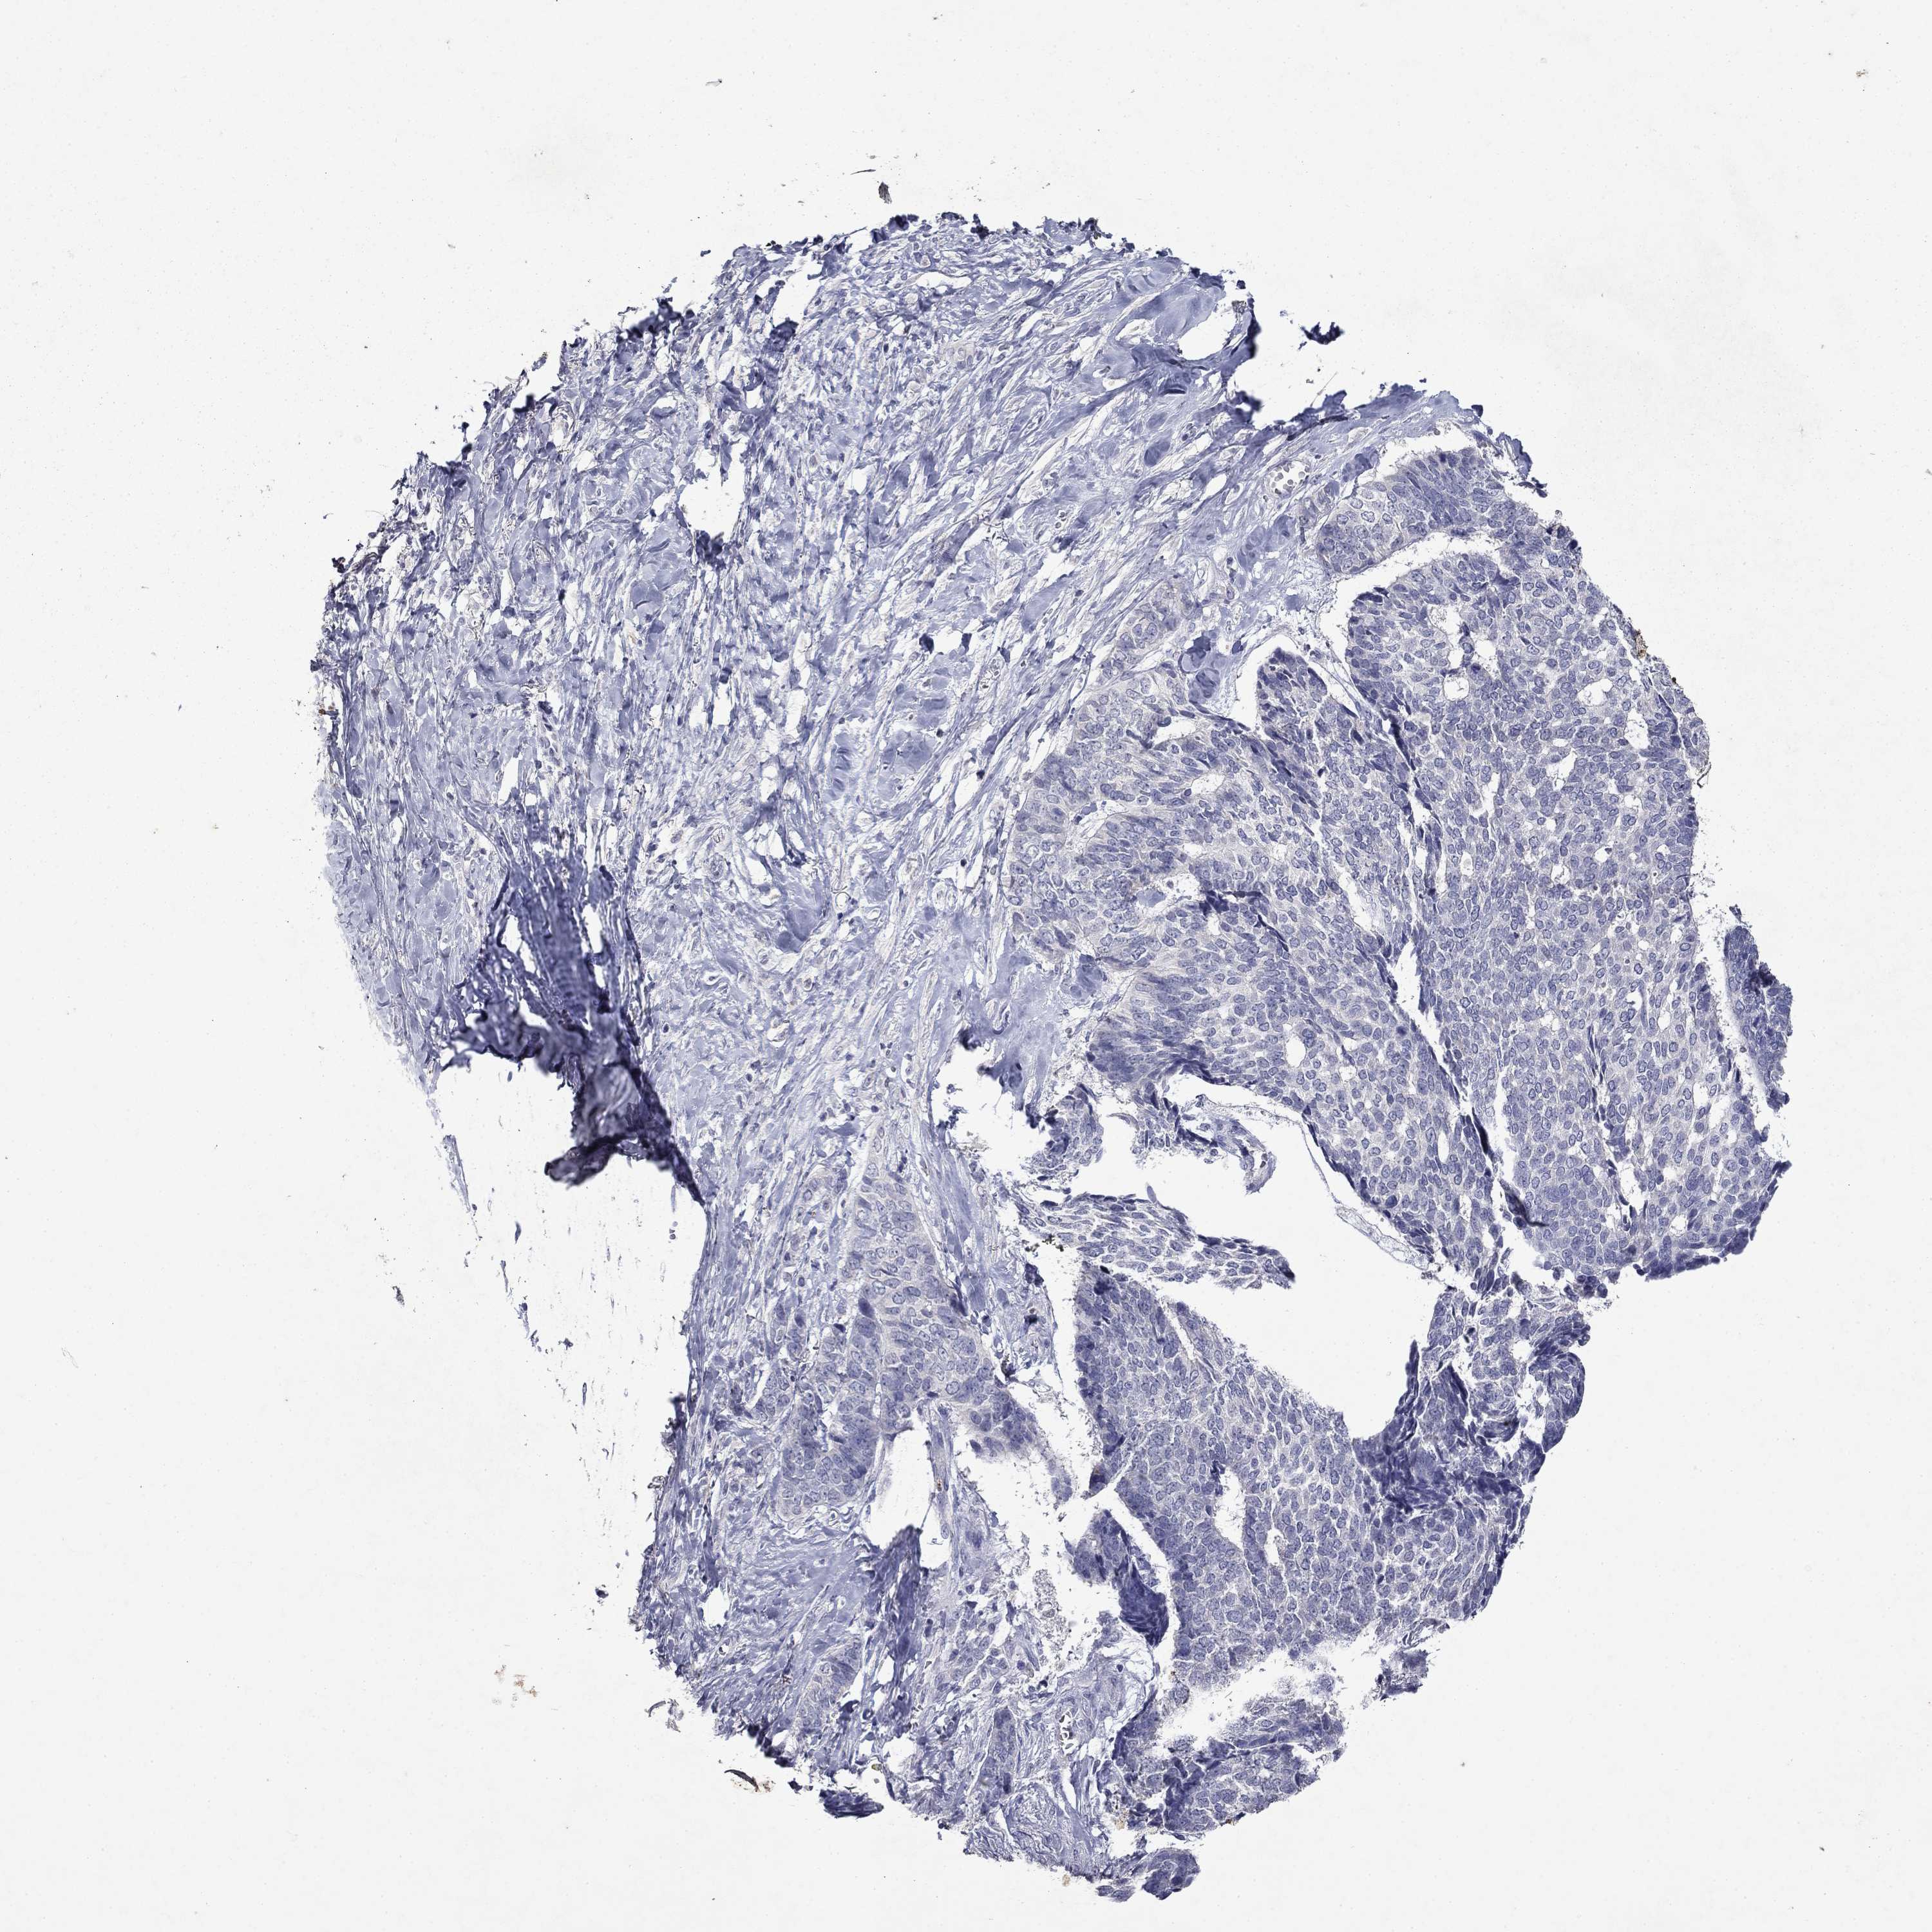

Basal cell and squamous cell cancer

SKIN CANCER - Protein expressioni

A mouse-over function shows sample information and annotation data. Click on an image to view it in a full screen mode. Samples can be filtered based on level of antibody staining by selecting one or several of the following categories: high, medium, low and not detected. The assay and annotation is described here.

Each image is clickable and will lead to virtual microscopy that enables deeper exploration of all samples and also displays staining intensity scores, fraction scores and subcellular localization as well as patient and tissue information for each sample.

Antibody HPA046700

Basal cell carcinoma